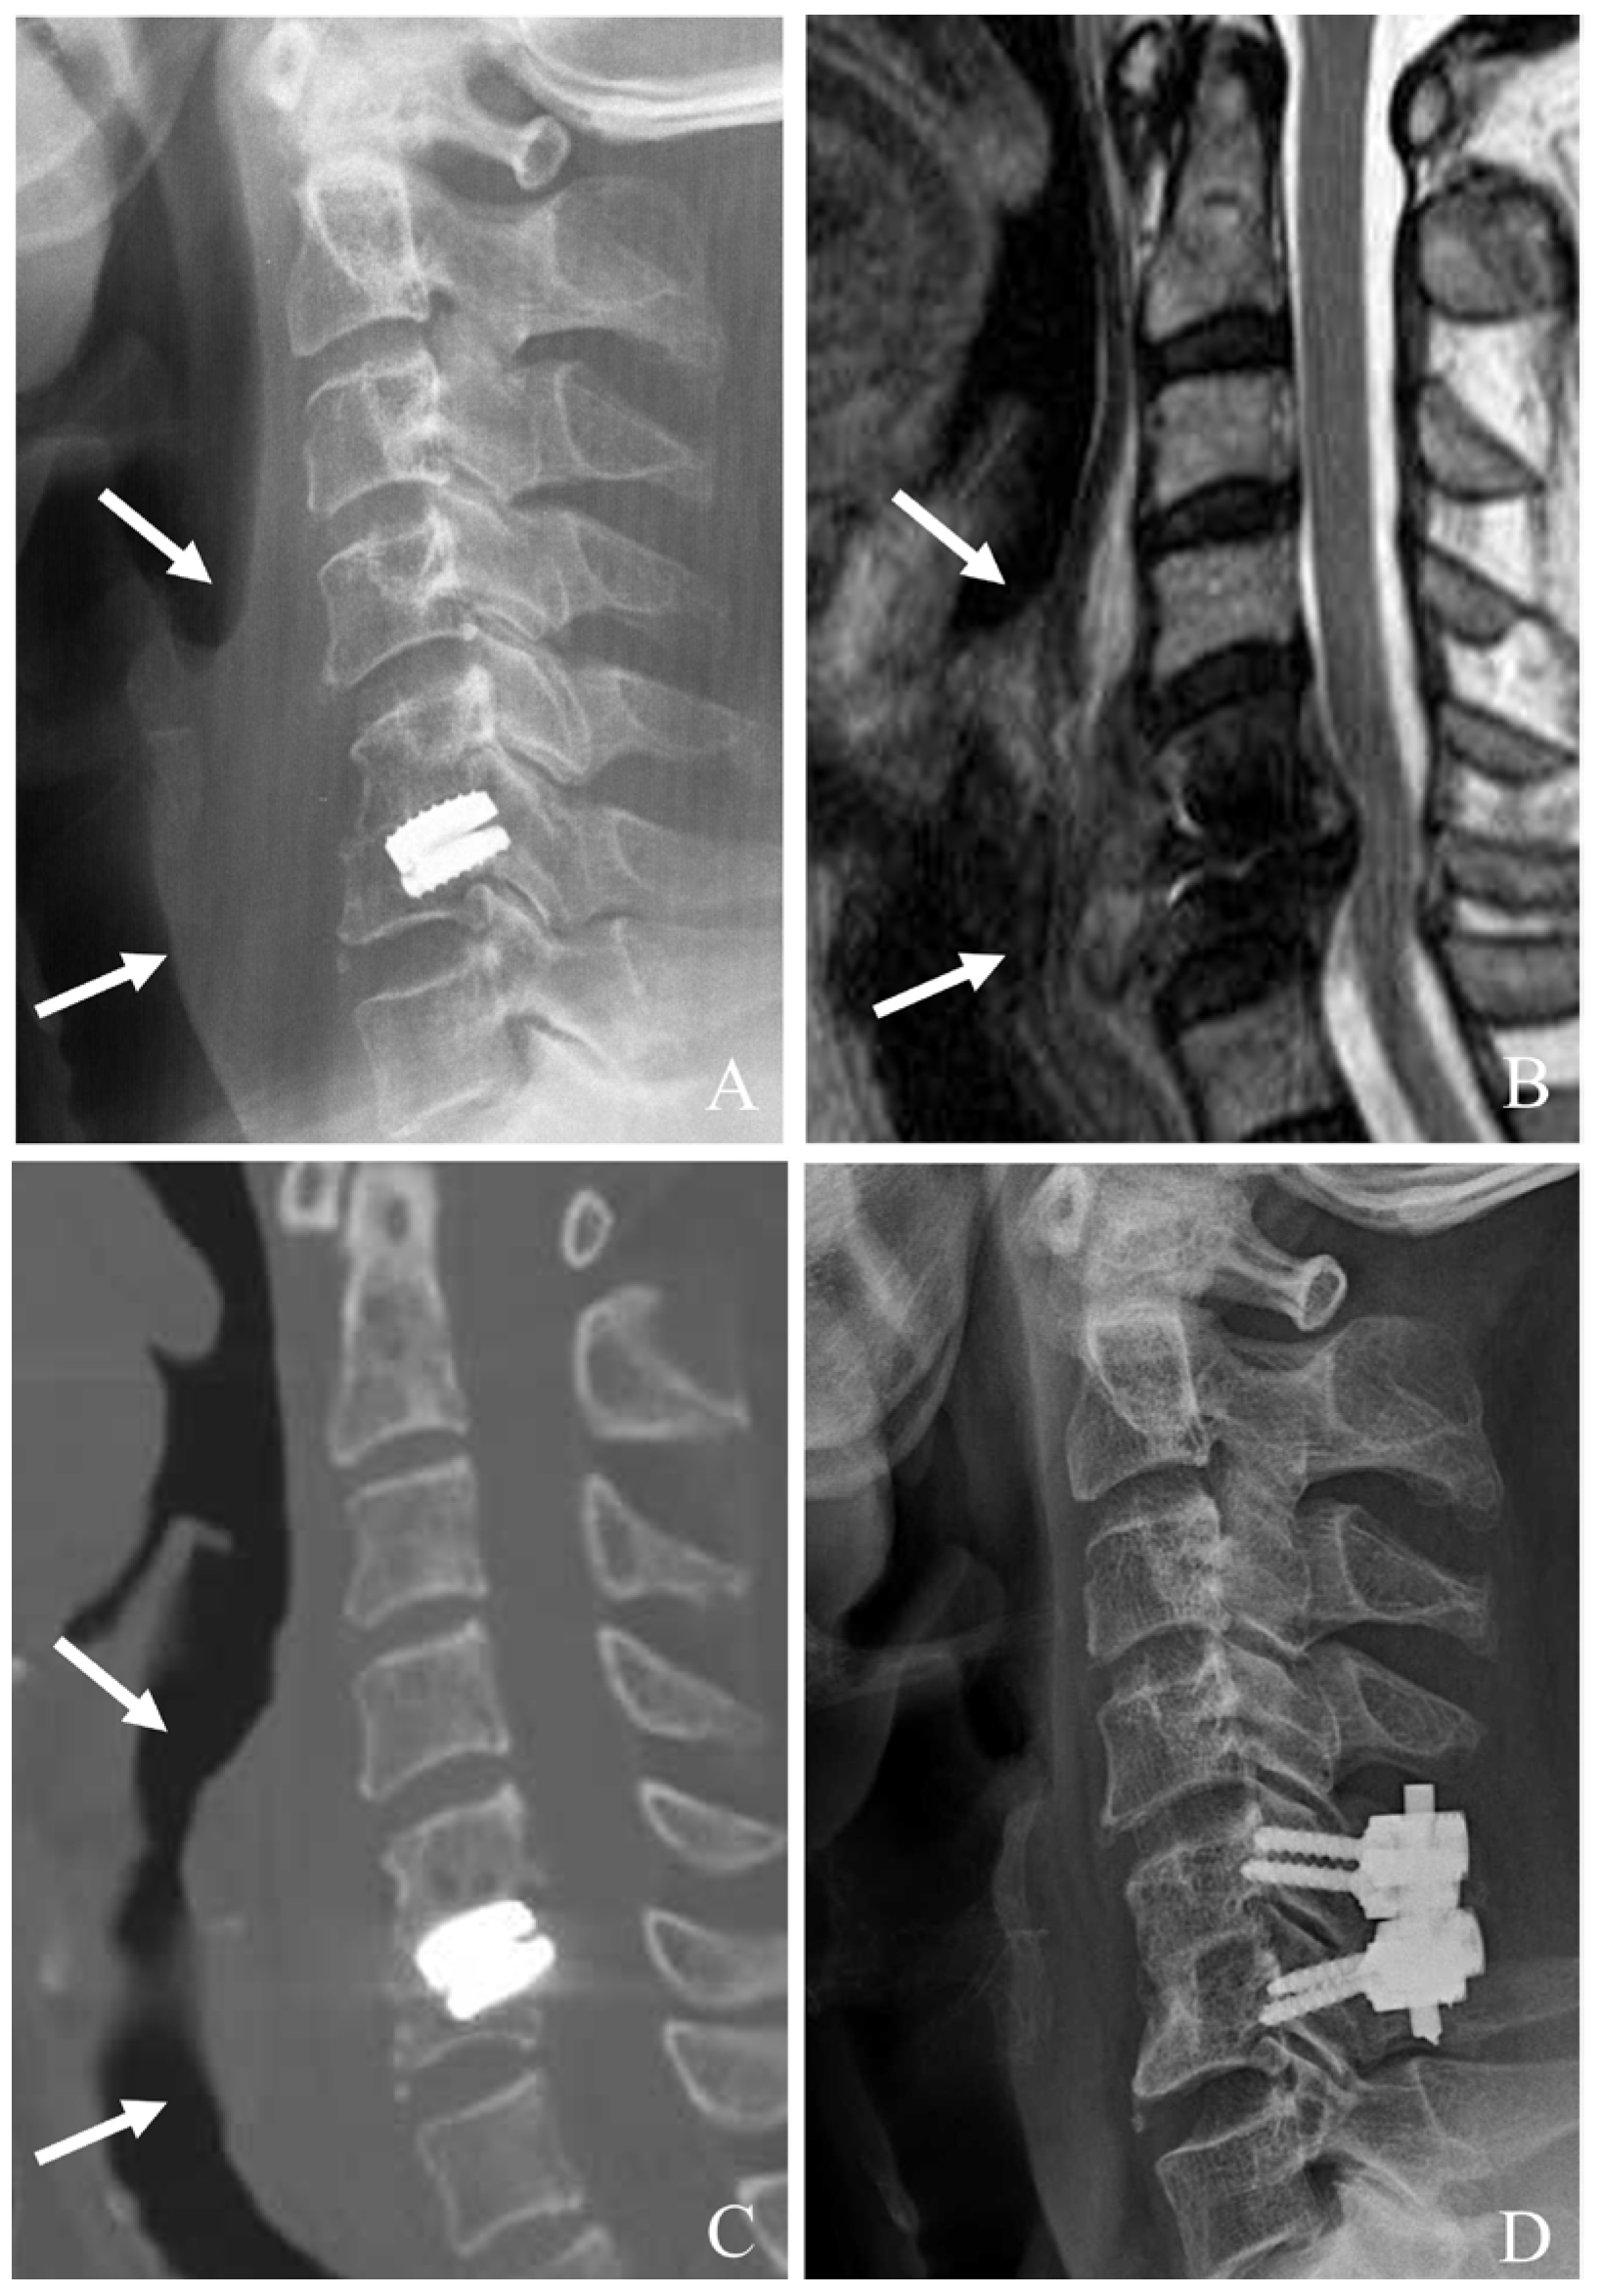

5.3. Posterior Cervical Decompression and Fusion (PCDF)

When CDA fails at the index level, PCDF is a well-established surgical option, particularly in cases where anterior reoperation is either contraindicated or insufficient [22,23,24,25,26]. PCDF provides robust neural decompression and stabilization, making it especially useful for cases with instability, deformity, or posterior element involvement (Figure 3). Although this approach is more invasive than anterior reoperations, it offers comprehensive management of those with complex failure mechanisms.

Figure 3. Plain X-rays (A), computed tomography (B), and magnetic resonance image (C) showing cervical disc arthroplasty at C5–6 and C6–7 and severe foraminal stenosis and posterior osteophytes (white arrows). The patient underwent C4–7 posterior cervical laminectomy, foraminotomy, and fusion with C3–7 pedicle screw fixation (D).

Figure 4. Plain X-rays (A), magnetic resonance image (B), and computed tomography (C) showing subsidence and retropulsion of cervical disc arthroplasty at C5–6 with retropharyngeal (white arrows) and epidural abscess causing cord compression. The patient underwent the removal of the C5–6 prosthesis and combined C5–6 anterior cervical discectomy and fusion and posterior fusion with lateral mass screws (D).